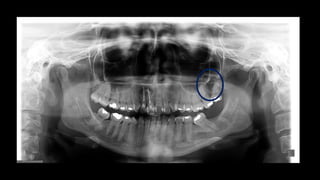

Os ceratocistos odontogênicos exibem uma área radio lúcida, com margens escleróticas

frequentemente bem definidas. Lesões grandes, particularmente no corpo posterior e no

ramo da mandíbula, podem se apresentar multiloculadas.

Os ceratocistos odontogênicosexibem uma área radio lúcida, com margens escleróticas frequentemente bem definidas. Lesões grandes, particularmente no corpo posterior e no ramo da mandíbula, podem se apresentar multiloculadas.